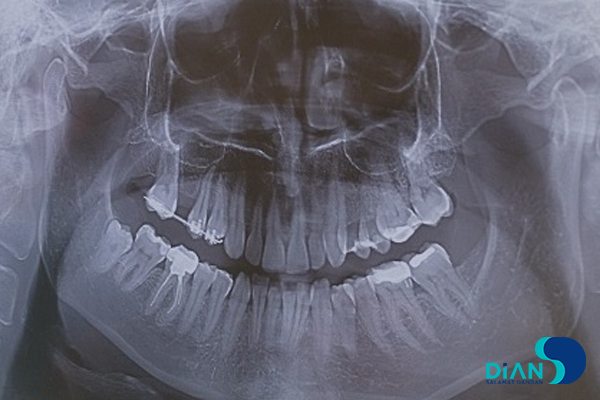

The experienced dentist Dr. Müesser Aktaş from Turkey successfully performed a dental implant procedure using Bio3 Implants in the molar region. For this operation, Dr. Aktaş utilized the Bio3 surgical kit, which is specifically designed to provide precision, ease of use, and efficiency during implant placement. The system’s user-friendly design and reliable components allowed for a smooth and accurate procedure, ensuring optimal results for both the patient and the clinician. This case once again highlights the practicality and advanced engineering of Bio3 Implants, making them a trusted choice for dental professionals worldwide.

Implantation in Molar Area